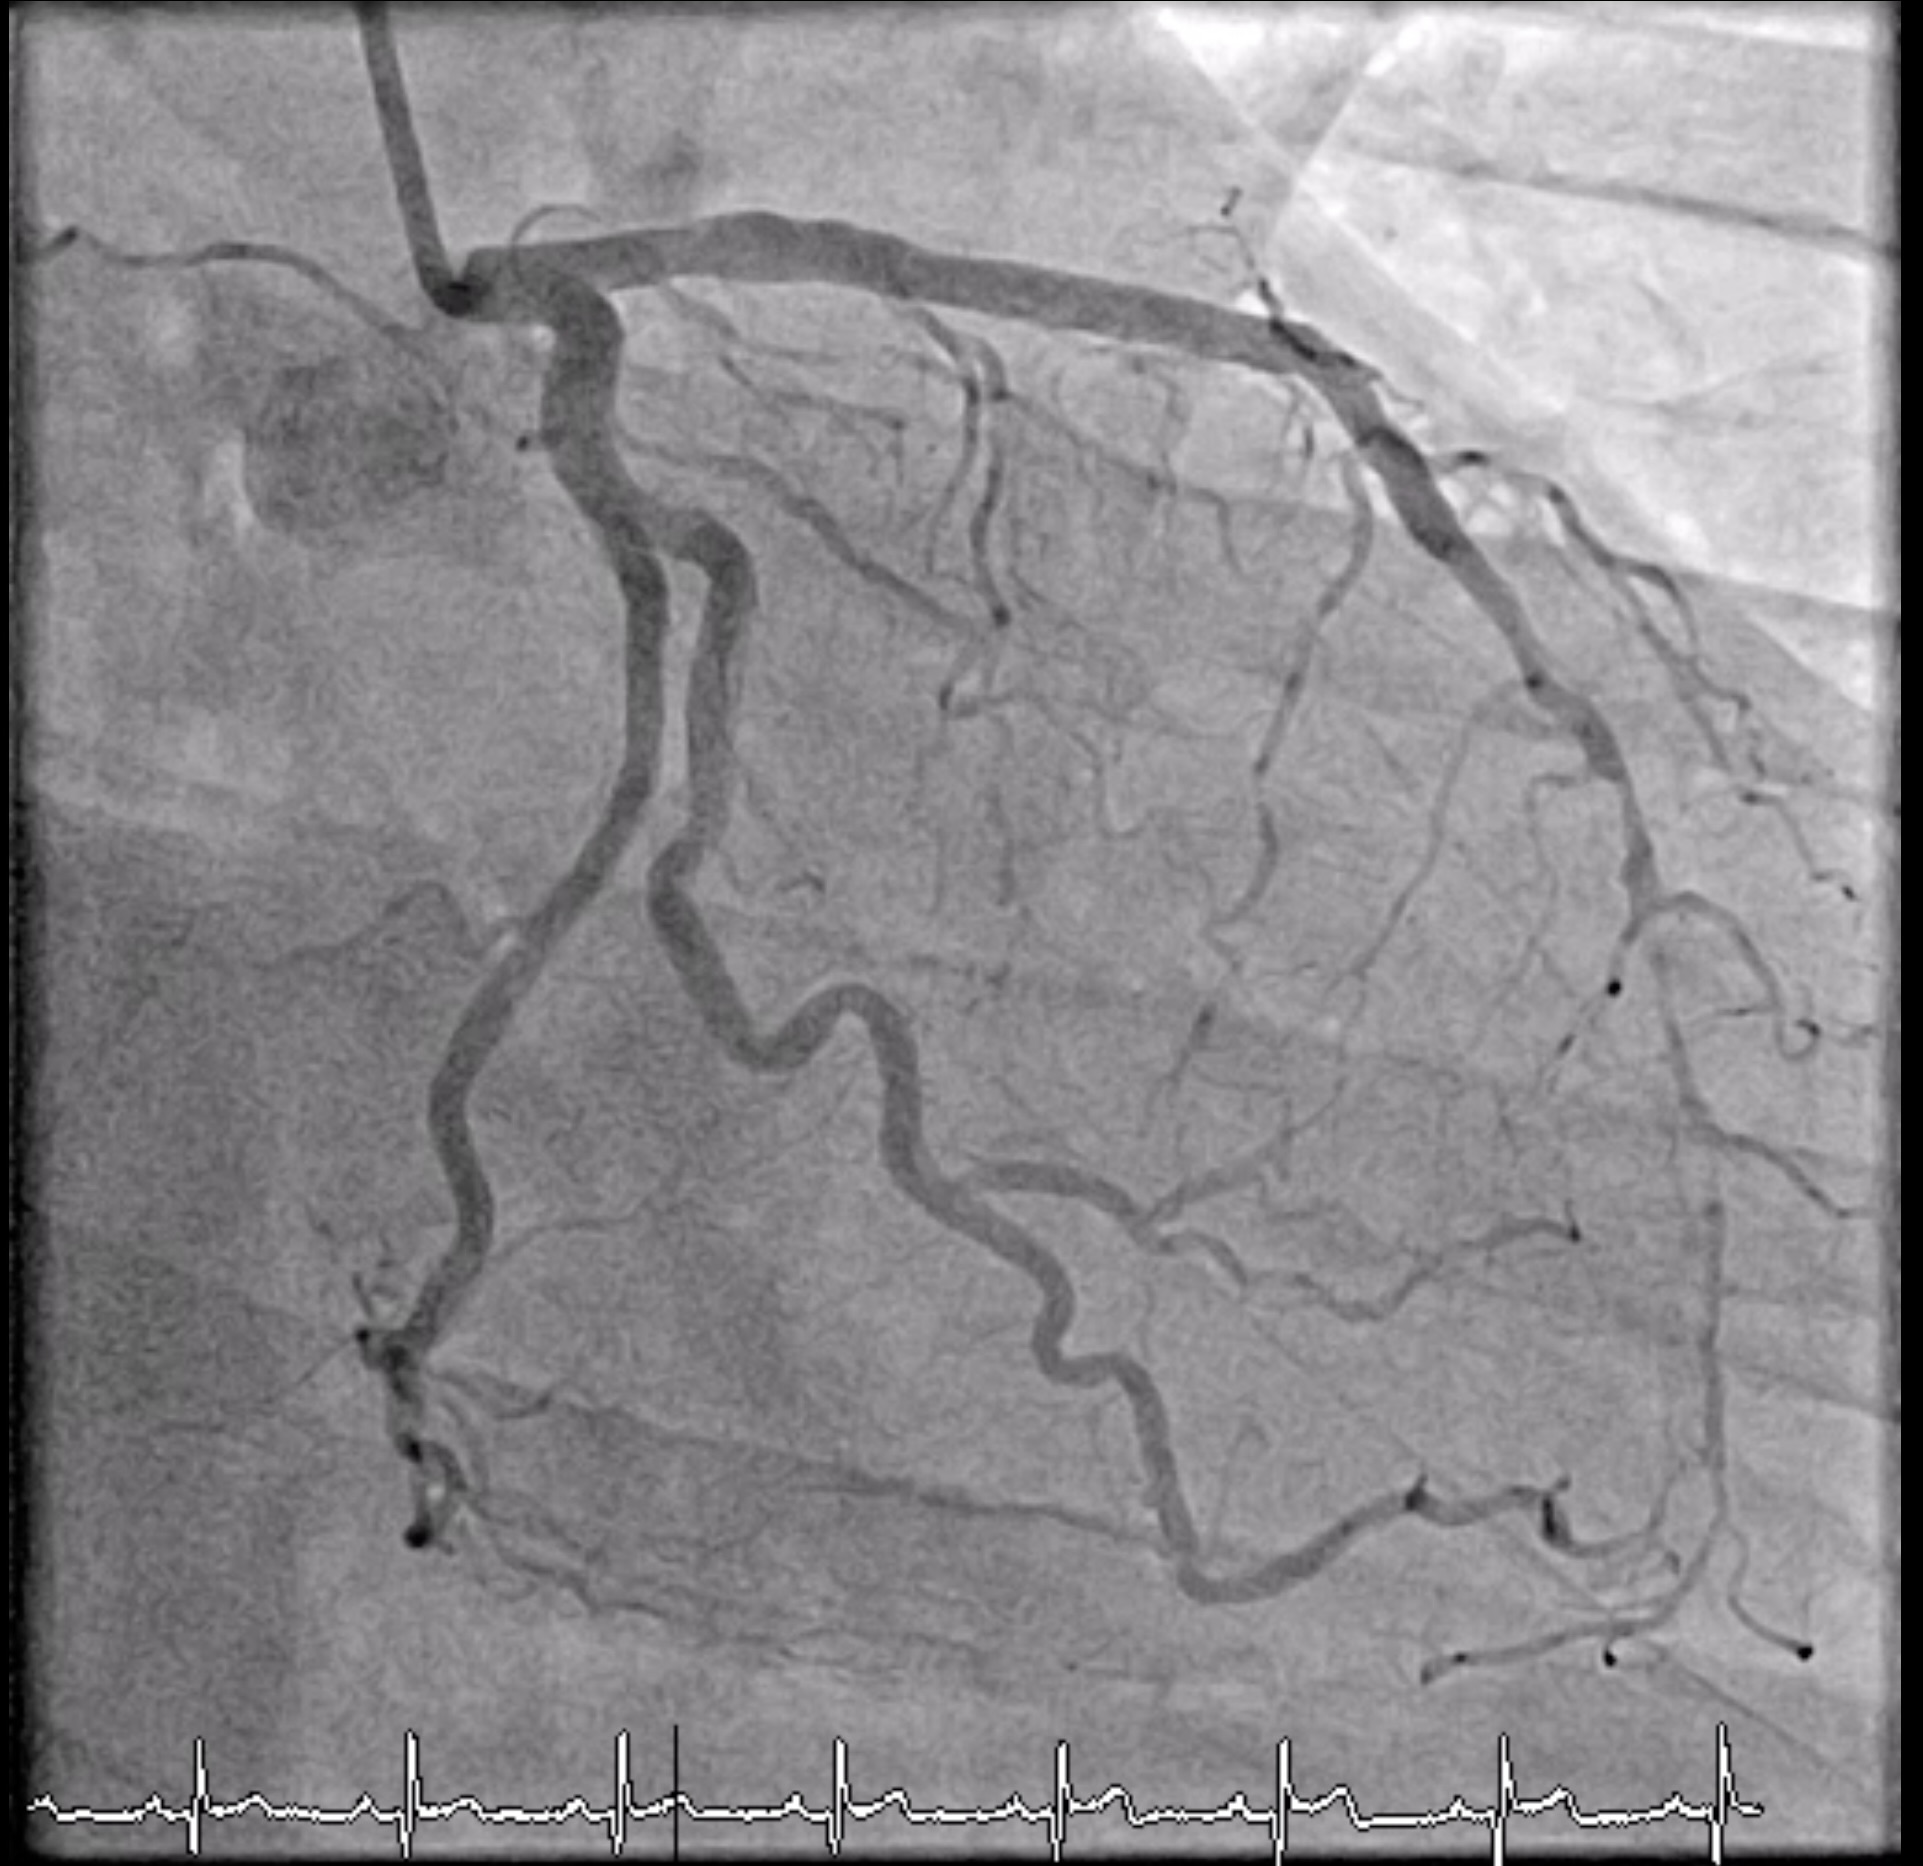

LM: NormalLAD: Patent proximal to mid-LAD stentLCx: No significant stenosisRCA: Patent stent at proximal RCA, CTO mid to distal RCA, receive collateral to PL and PDA from LAD